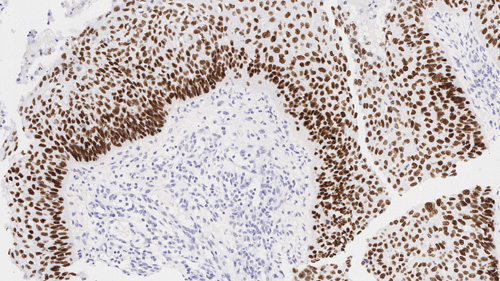

PGR-312-L-CE

1ml NCL-L-PGR-312